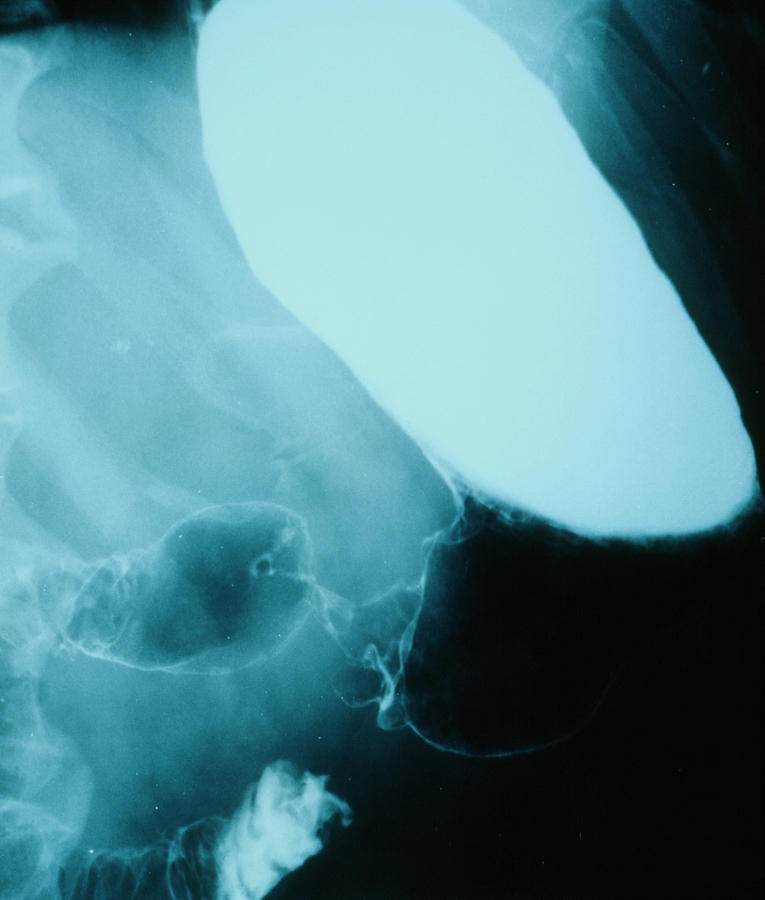

from www.sciencephoto.com

Normal stomach, barium Xray Stock Image C001/7145 Science Photo